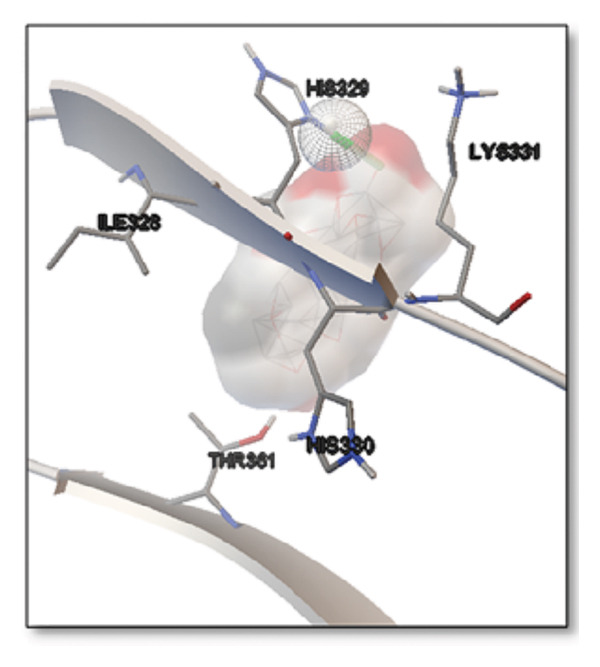

For the tau protein repeat domain, ginkgolide recorded a strong binding energy of −10.63 kcal/mol, with a key stabilizing interaction involving HIS329. This interaction was characterized by a D–A distance of 3.05 Ǻ and an excellent angle of 170.04°. Other top binding compounds included ginsenosides (−6.28 kcal/mol), also interacting with HIS329 and PRO364, and galantamine (−5.47 kcal/mol), forming bonds with VAL337 and VAL339. Berberine bound at −5.33 kcal/mol via GLN351. Apigenin exhibited favorable interaction with the tau repeat domain via a hydrogen bond with ILE 328 (D–A: 2.91 Ǻ; angle 161.21°), highlighting the high quality of the interaction. Among the reference drugs, donepezil bound at −5.34 kcal/mol. Figure 5 details the binding characteristics for tau protein.

Histidine residues are frequently involved in coordinating chaperone‐substrate interactions. The binding of ginkgolide at HIS205 suggests it may stabilize the active conformation of the chaperone, thereby enhancing its ability to bind to and inhibit the formation of amyloid fibrils, a key mechanism reinforced by recent research published [ref. 40]. This research has consistently reinforced that clusterin’s ability to bind to and inhibit the formation of amyloid fibrils is a key mechanism of action, particularly in neurodegenerative diseases. While direct mention of HIS205 is rare, its chaperone function is broadly understood to rely on such key residues. Elias et al. [ref. 41] and Carini et al. [ref. 42] confirm that clusterin’s role in inhibiting aggregation is a major focus of current research. Finally, the predicted binding to HIS329 in tau is highly significant and directly corroborated by recent literature. HIS329 is explicitly located within the microtubule‐binding repeat domain, which is the primary site for tau’s pathological self‐aggregation. Ginkgolide’s predicted binding at this position is a direct mechanism of aggregation inhibition, suggesting it acts as a steric wedge or “capping agent” to prevent the formation of toxic beta sheet structures, aligning with similar strategies explored. Studies have explicitly identified histidine residues within the microtubule‐binding repeat domain as participants in tau’s self‐aggregation process. Hernández et al. [ref. 43] specifically names residues like H329 as being involved in this mechanism. Molecular docking and simulation studies, such as one from 2025 by Saha and Natarajan [ref. 44], also focus on targeting this domain with small molecules to inhibit tau pathology, providing strong support for the in silico predictions.